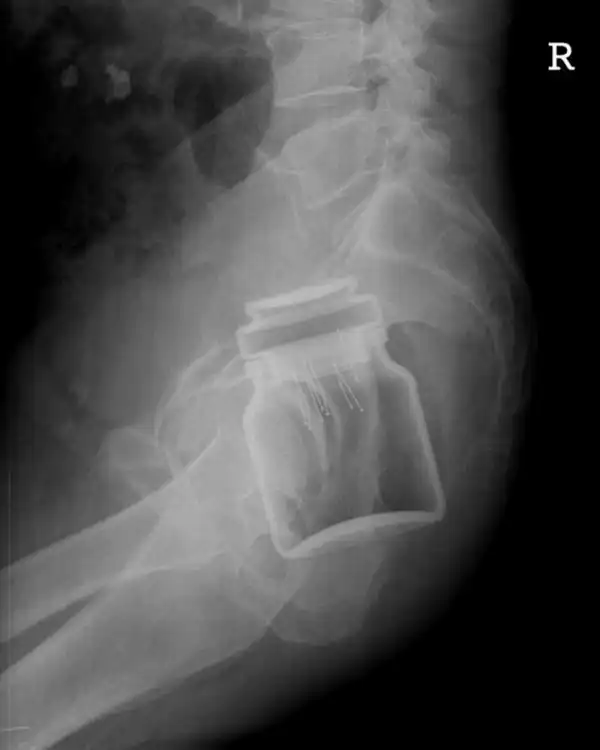

Может, была Пасха?

Повезло человеку - выжил

Аномальный снимок